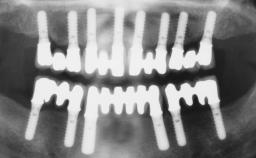

Immediate Loading of Four Implants in the Mandible and Final Restoration with a Full-Arch Metal Framework FDP

A fully edentulous 65-year-old woman was referred to our clinic for esthetic and functional dental rehabilitation. The patient presented with inadequate complete maxillary and mandibular prostheses, insufficient vertical dimension, and extensive tooth wear. The clinical examination and anamnesis showed no local or systemic contraindications, no signs or symptoms of bruxism, and an absence of smoking habits. The treatment proposed was implant placement in the mandibular interforaminal area and immediate loading with a fixed definitive prosthesis. A removable mucosa-supported complete prosthesis was indicated for the upper jaw, since its bone structure offered satisfactory retention and the financial condition of the patient disfavored a full-mouth implant-supported rehabilitation.

# of Implants 4

Type of Implants One-Piece